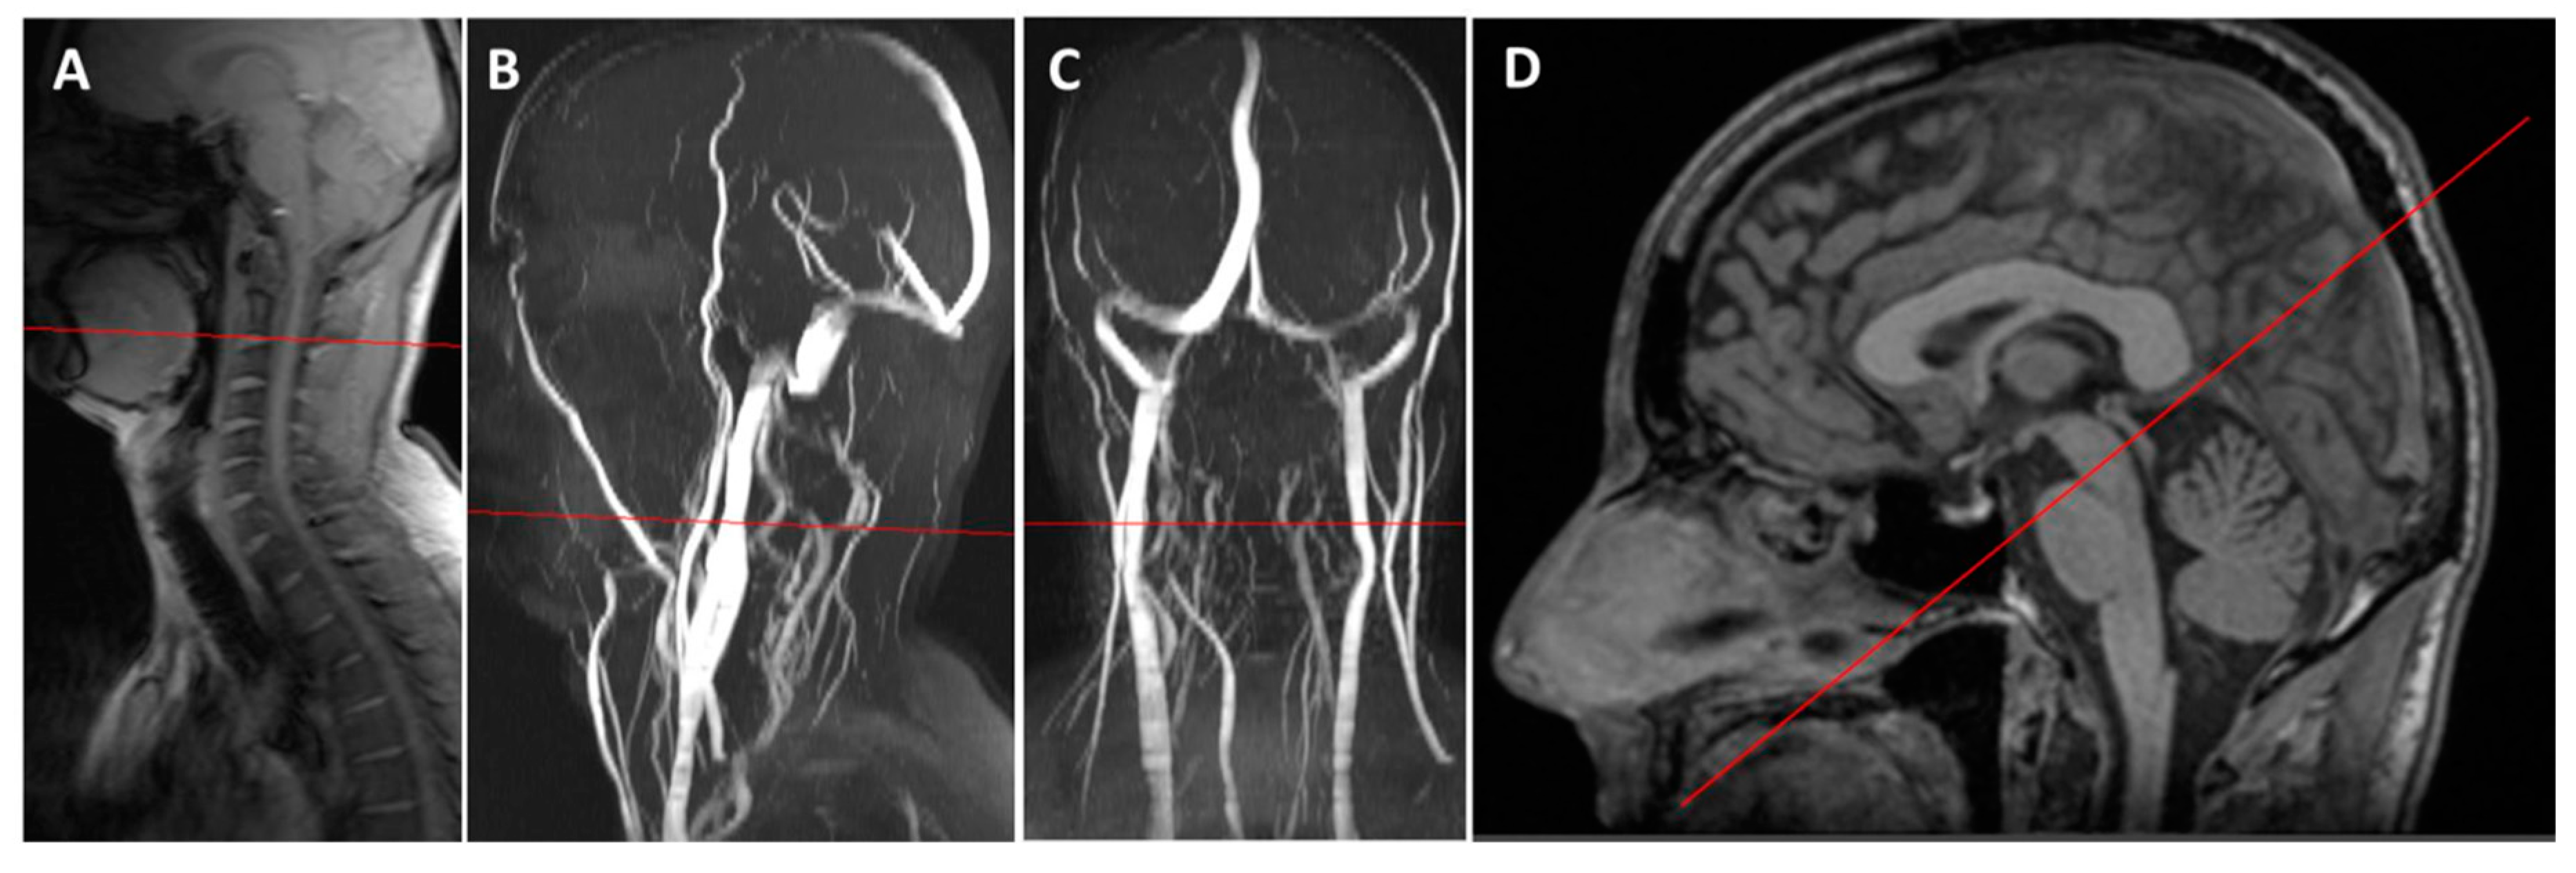

2.2. Magnetic Resonance Acquisition and Processing

3.2. Magnetic Resonance Imaging Results